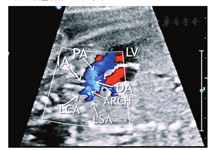

孕妇,27岁,孕1产0,孕25周。行产前超声检查示:胎儿如孕25+4周,腹部横切面显示腹主动脉与下腔静脉位置排列关系正常,腹腔脏器正位;四腔心切面显示心尖指向左侧,房室大小正常;心室流出道切面显示升主动脉(内径3.3 mm)及肺动脉大部分(内径6.7 mm)发自右心室,比例(PA/AO)为2.03,两者起始部呈平行排列,室间隔上部中断4.9 mm,肺动脉骑跨于室间隔上;彩色多普勒示左心室血流经过室间隔缺损直接射入肺动脉内(图1,图2);三血管及三血管气管切面显示主动脉位于肺动脉右前方,与动脉导管共同形成"V"形血管结构消失,多切面检查主动脉弓于左锁骨下动脉以下未能与降主动脉连续,无法显示完整的主动脉弓长轴切面(图3)。超声诊断:胎儿心脏发育异常,右心室双出口(Taussig-Bing型)、室间隔缺损、升主动脉发育不良、主动脉弓离断(A型)可能性大。胎儿引产后,心脏解剖证实超声诊断(图4)。

右室双出口是一种少见的先天性心脏病,约占先天性心脏病的5%[1],是指两支大动脉全部或一支大动脉完全加另一支大动脉大部分起源于形态学右心室。根据两支大血管在半月瓣水平的解剖关系和室间隔缺损的解剖类型准确诊断Taussig-Bing型右室双出口一般不难。但右室双出口常常合并心内外畸形且无器官系统特异性[1]。因此在诊断右室双出口后还应注意仔细扫查心内外结构是否异常,如本例合并升主动脉发育不良并主动脉弓离断A型。主动脉弓离断是一种较为罕见的先天性心脏病,产前诊断难度较大。本例根据三血管切面"V"形血管结构消失、主动脉内径变窄、PA/AO>2,多切面检查主动脉弓于左锁骨下动脉以下不能与降主动脉连续,无法显示完整的主动脉弓长轴切面等而考虑主动脉弓离断[2]。本例胎儿经引产后尸体解剖证实为右室双出口Taussig-Bing型并主动脉弓离断,系两种罕见心脏畸形并存。笔者体会到:只要准确掌握胎儿心脏的标准切面,通过三节段六连接的分析方法,基层医院超声医师也能正确诊断宫内胎儿心脏复杂畸形。